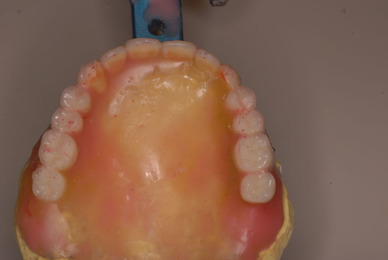

¤ª¸ý¤ÎÃæ¤«¤éº¹¤·»õ¡¢Æþ¤ì»õ¡¢µÍ¤áʪ¤òÄÉÊü¤·¤Þ¤·¤ç¤¦¡ª

¸ý¤ÎÃæ¤Îɵ¤¤ò¼£¤·¡¢Éµ¤¤ò¶½¤µ¤Ê¤¤°åÎŤòÌܻؤ·¤Þ¤¹¡£

ÆóÅ٤Ȥª¸ý¤ÎÃæ¤ØÊѤʤâ¤Î¤òÆþ¤ì¤Ê¤¯¤Æ¤âºÑ¤à¤è¤¦¤Ë

ͽËɤËÀº¿Ê¤¤¤¿¤·¤Þ¤·¤ç¤¦¡ª°ÂÁ´¤Ê¶ºÀµ¡¢ÈþÍÆ¤òÌܻؤ·¤Þ¤·¤ç¤¦¡ª